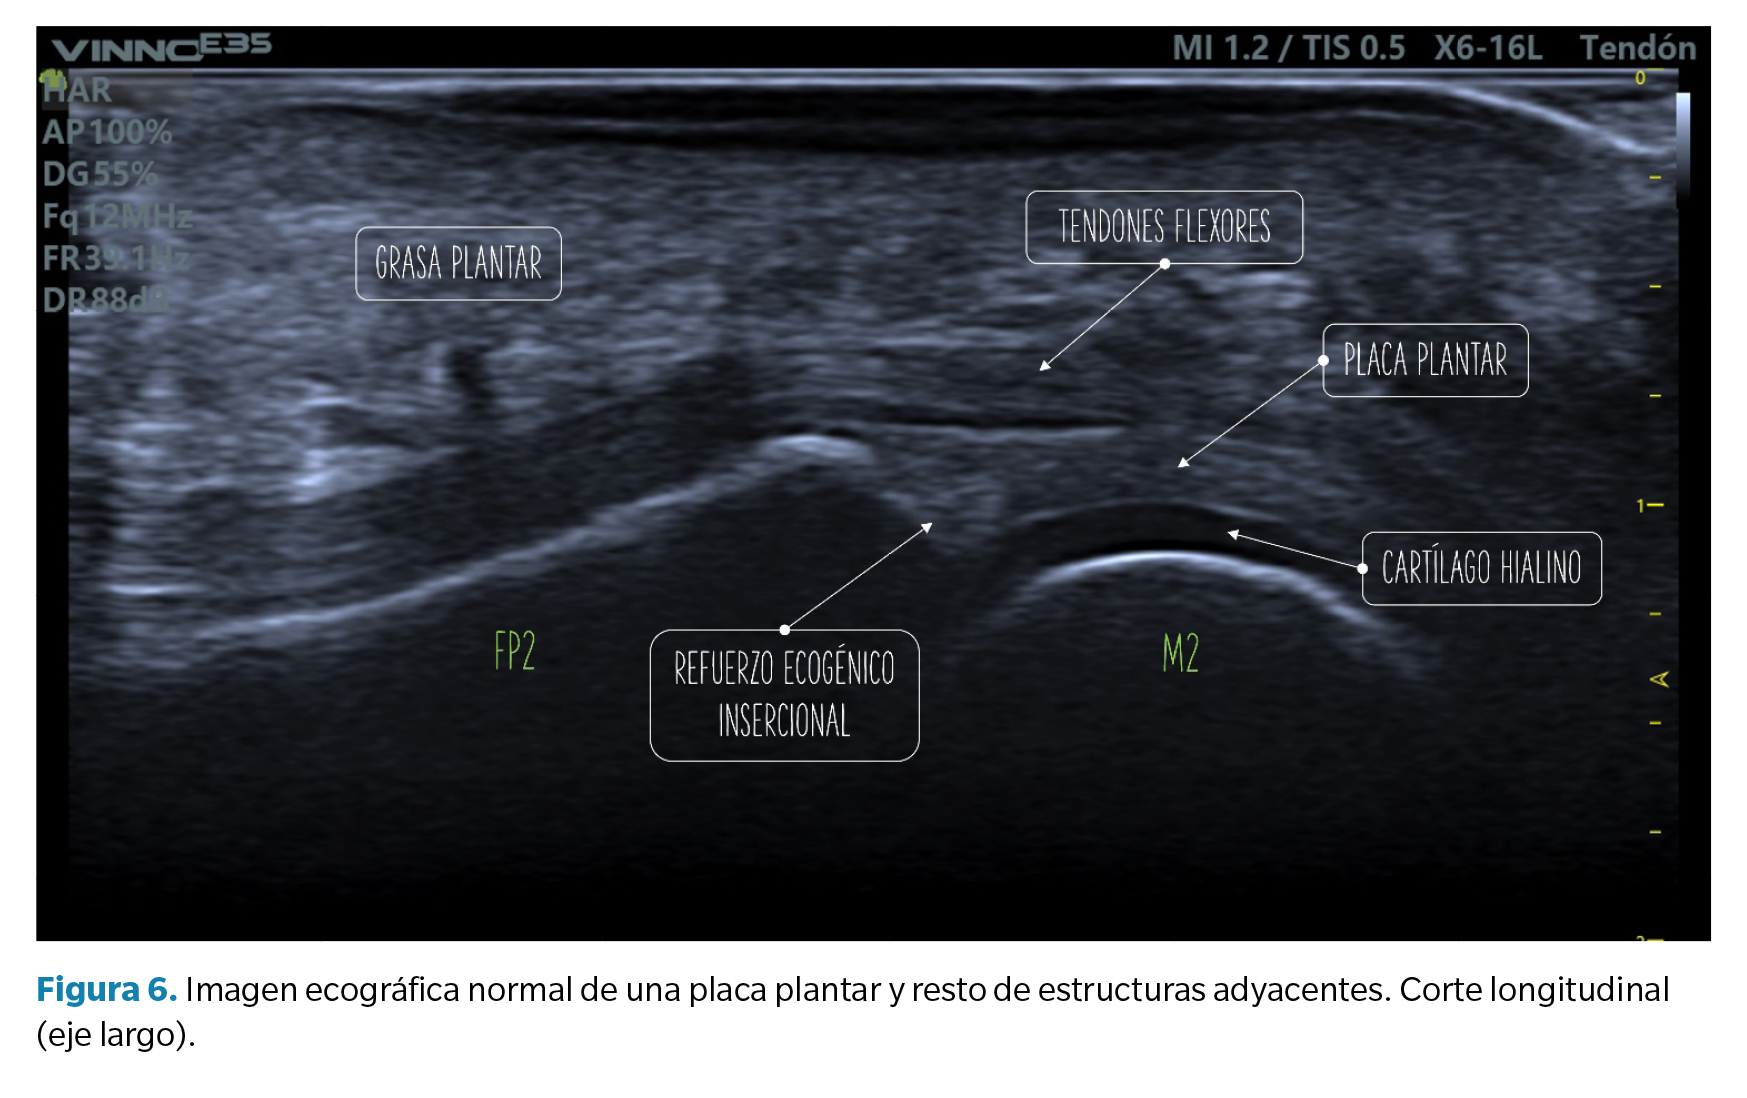

• Corte longitudinal (eje largo): la placa plantar normal se muestra ecográficamente como una estructura curvilínea ligeramente ecogénica con ecotextura granulada homogénea. Esta textura permite la diferenciación, no siempre definida, con los tendones flexores subyacentes de textura fibrilar. La superficie articular de la placa se define con precisión limitando con el cartílago hialino de la cabeza metatarsal, hipoecoico (Figura 6).

En la unión con la falange proximal, bien definida, el contorno óseo es normalmente liso y en la placa puede aparecer una zona triangular más ecogénica que se ha descrito como un hallazgo ecográfico normal y podría representar una mayor proporción de fibras de colágeno. La unión proximal al cuello metatarsal, en cambio, tiene una definición pobre en imagen ecográfica (Figura 6).